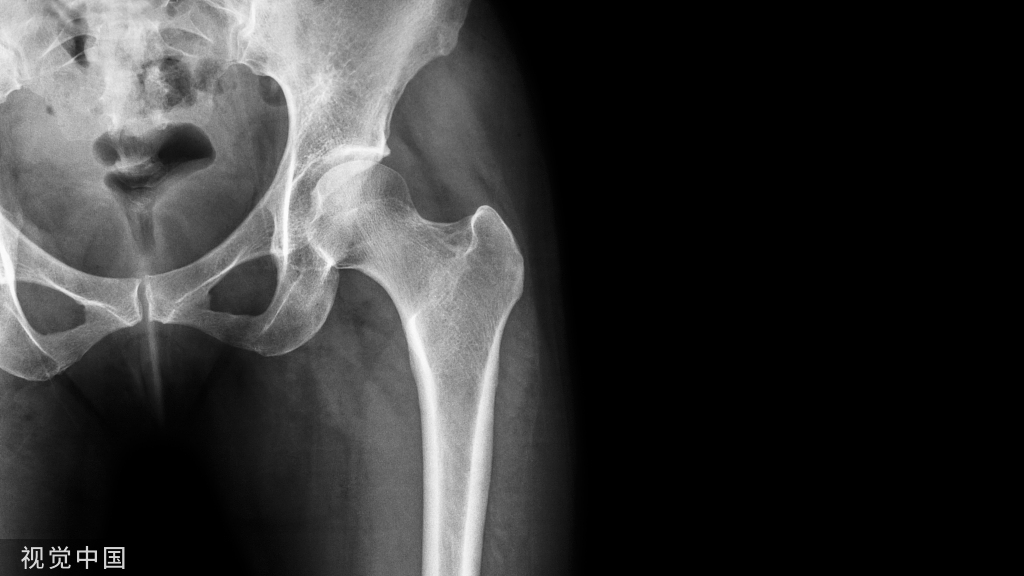

老年髋部骨折是一种常见且严重的骨折,今天我们就从五大要点全面了解老年髋部骨折的围术期管理!

患者髋部骨折分为囊内和囊外两种类型。囊内骨折包括头下型、头颈型和经颈型,骨折后出血少。

移位不明显的囊内骨折可考虑保守治疗,但再脱位率高达30%~50%。无移位的囊内型骨折可考虑内固定或滑动髋螺钉。手术方式可选半髋关节置换,但囊内骨折远期易发关节炎,因此对于非高龄患者可考虑全髋置换。

囊外型骨折包括转子间和转子下骨折,碎裂程度越重出血越多,可高达1 L。由于骨膜撕裂程度重,其疼痛程度也较囊内骨折严重。外科手术治疗是囊外骨折的主要治疗措施。使用内固定患者1年内再手术率为23%,满意度较低,而选择关节置换后1年内再手术率仅为3%。